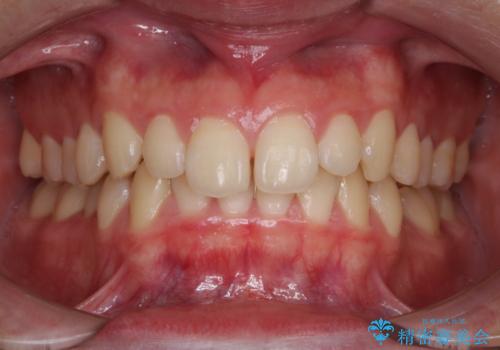

すきっ歯のワイヤー矯正による治療

- 前歯の隙間を閉じたいとのことで来院されました。

ワイヤー矯正にてスペースを閉じで、上下の歯のかみ合わせを改善することとなりました。

矯正治療には多少の痛みが伴いましたが、隙間もなくきれいな歯並びへと改善されました。